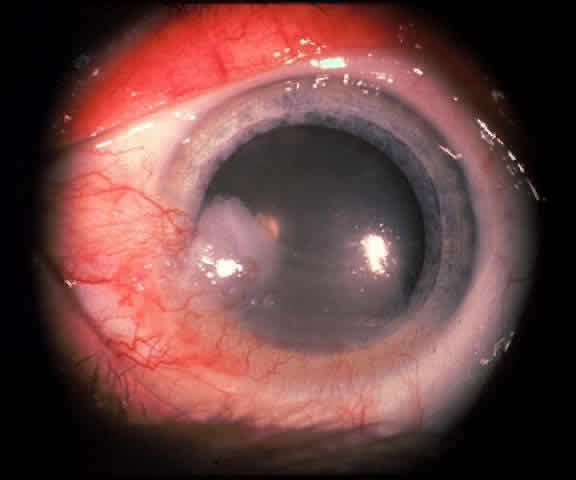

The epithelial dysplastic lesions—conjunctival intraepithelial neoplasia and squamous cell carcinoma—almost always begin at the limbus, most commonly in the interpalpebral zone.57,58 The initial appearance is a gelatinous, gray lesion with some thickening (Fig. 3). There may be increased vascularization. The epithelial changes may extend onto the cornea, causing a hazy, gray appearance. Tumor vascularity lags behind the lead margin of the epithelial change. As the lesions progress from dysplastic to carcinomatous, they become thicker, more vascularized and may show keratinization, giving a leukoplakic appearance (Fig. 4). Lesions confined to the epithelium move freely over the sclera, whereas invasive lesions are fixed to underlying tissue. Occasionally squamous cell carcinomas appear identical to classic papillomas.

Fig. 8. Conjunctival intraepithelial neoplasia. Gray, gelatinous mass is centered at limbus and has prominent vessels. A veil of intraepithelial disease extends laterally across the inferior third of the cornea.

Fig. 9. Squamous cell carcinoma of conjunctiva.

Early dysplastic lesions (conjunctival intraepithelial neoplasia) show thickened epithelium with extension of basal-like cells beyond the basal layer, but cells continue to mature into flat squamous cells. Mitoses are also seen higher in the epithelium. As the degree of dysplasia worsens, the more superficial epithelium is replaced at higher levels by basal-type cells, mitoses can be seen further from the basal layer, and atypia of cells becomes more pronounced. With squamous cell carcinoma in situ, there is full-thickness dysplasia, cellular atypia is variable, and mitoses can be seen at all layers of the epithelium. Invasive squamous cell carcinomas are usually well differentiated. Pleomorphism, hyperchromaticity, dyskeratosis, and horn pearls are seen. Epithelial cell clusters can be seen invading below the basement membrane. Inflammatory cells are common in the substantia propria.